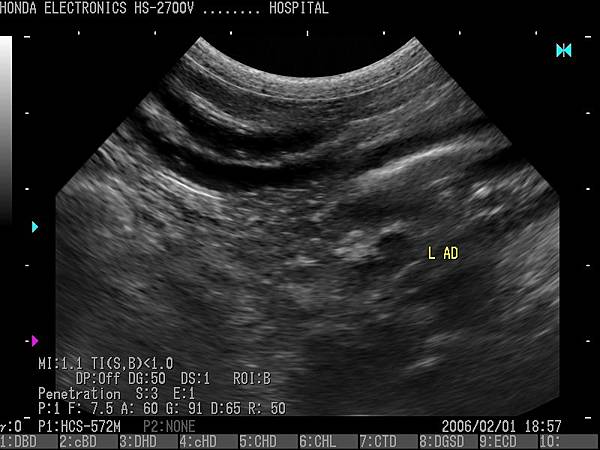

- 通過H-res獲得清晰豐富的單色圖像

HONDA獨創的圖像增強技術 H-res(我們的分辨率技術)

多年來超聲波技術的發展,結晶為“ H-res”圖像增強技術。

可以通過針對每種應用和探頭調整“ H-res”參數來獲得最佳圖像。